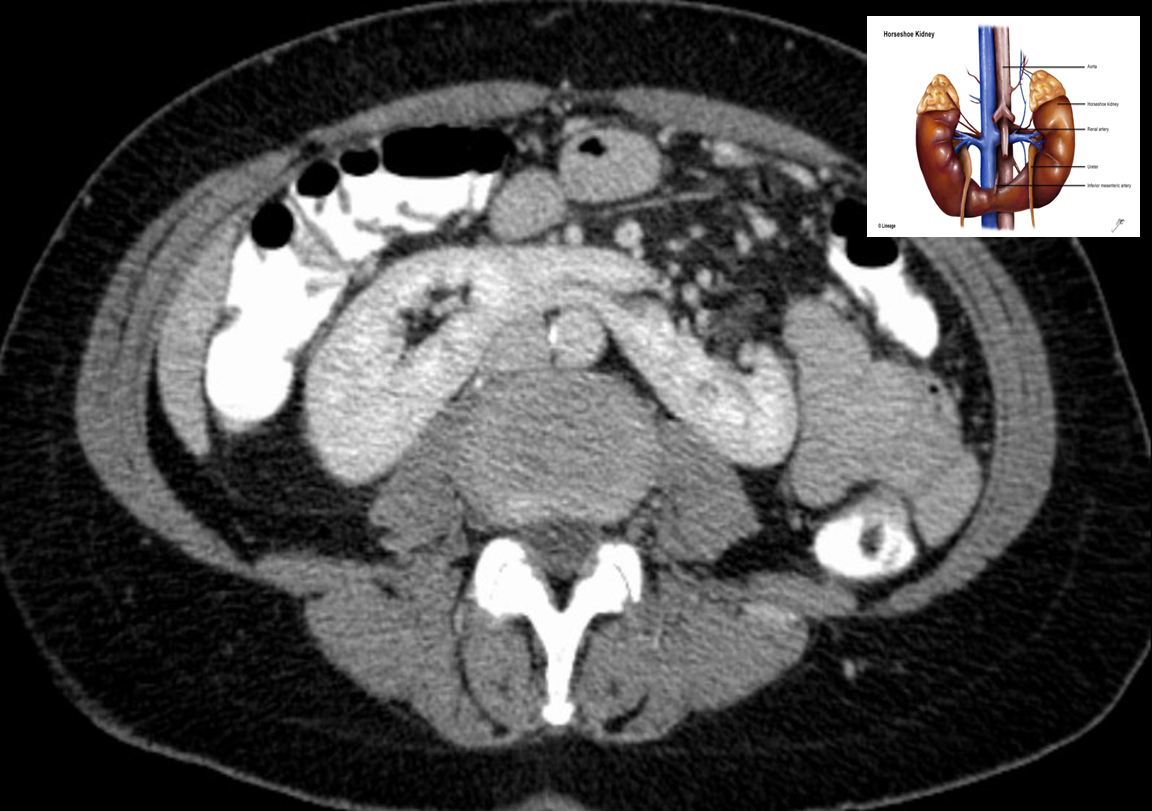

CT abdomen (with contrast; axial plane)

The lower poles of the kidneys are fused across the midline by an isthmus of enhancing parenchyma .

This is a classic appearance of horseshoe kidney.